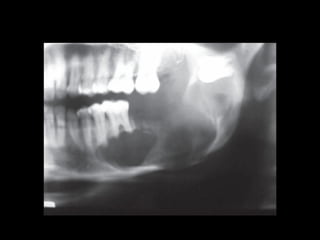

1. Radiographic evaluation, OPG shows multilocular

radiolucency with root resorption and

displacement of teeth

2. CT scan in case of larger lesions and esp maxillary

ameloblastoma